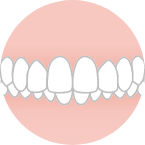

上の歯が出ている

覆いかぶさっている